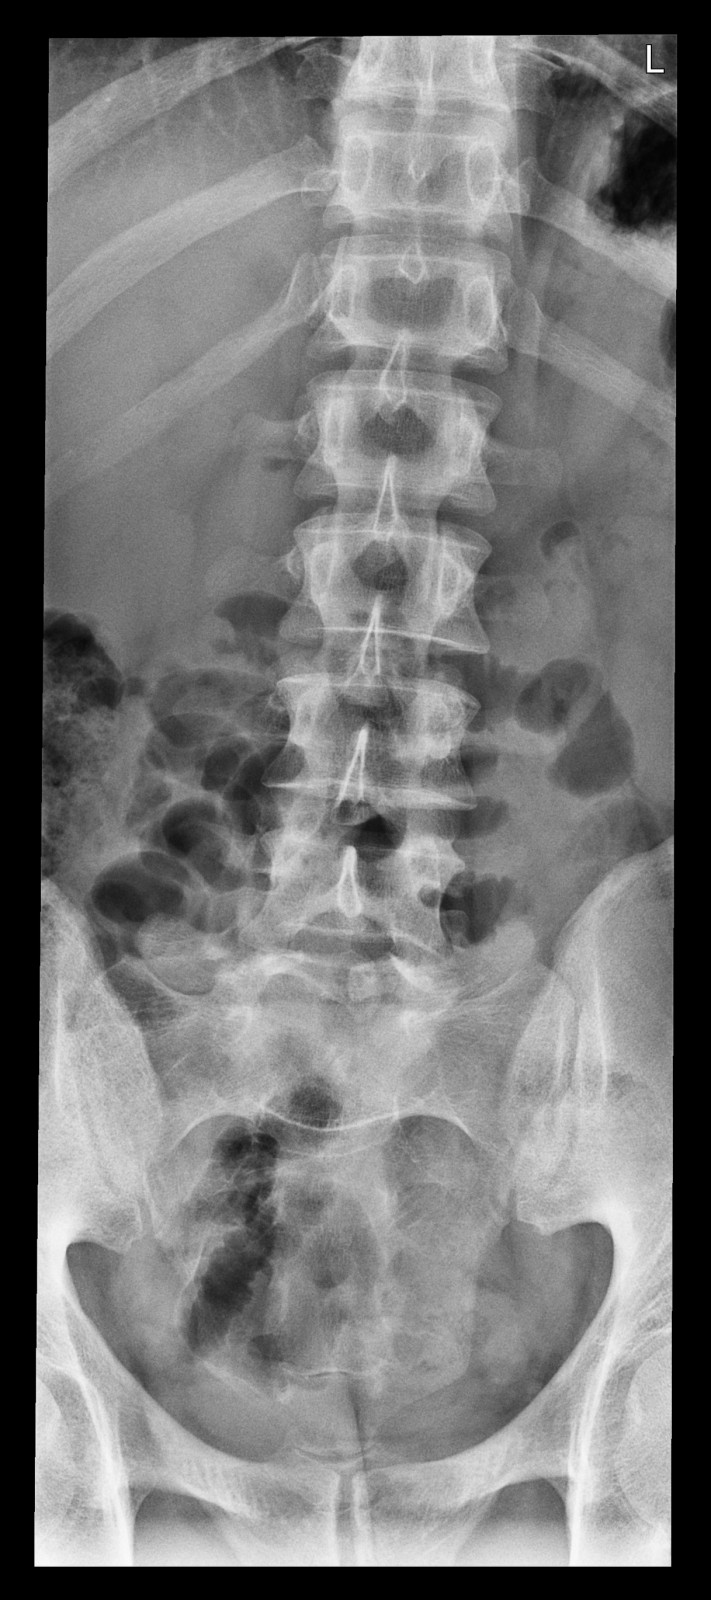

Röntgenfall des Monats Juni 2017 mit Auflösung

34 jähriger Patient mit exazerbierter Lumbago.

Beruf: Plattenleger